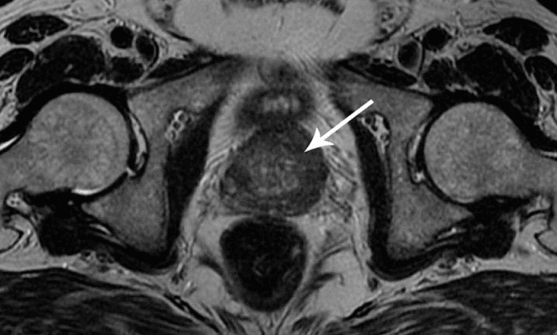

Dua t'ju tregoj disa foto per te demonstruar se cfare ndodh ne sistemin urogjenital dhe ne organet e tjera te nje burri qe nuk ben seks.

Ne foto shohim inflamacionin e prostates te shkaktuar nga stanjacioni i spermes (kur testikujt nuk zbrazen). Inflamacioni i vazhdueshem con fillimisht ne adenome te prostates dhe me pas ne kancer. Eshte pasoja e pashmangshme e prostatitit, dhe prandaj quhet "semundja e burrave te moshuar".

Kanceri i prostates te nje burre 58 vjec.

Staza shkakton depozitimin e kolesterolit ne muret e eneve te gjakut, gje qe mund te coje ne ngushtimin e lumenit te tyre dhe ne formimin e mikrotrombeve. Kjo perkeqeson ushqyerjen e gjendres se prostates dhe kontribuon ne zhvillimin e inflamacionit ne te.